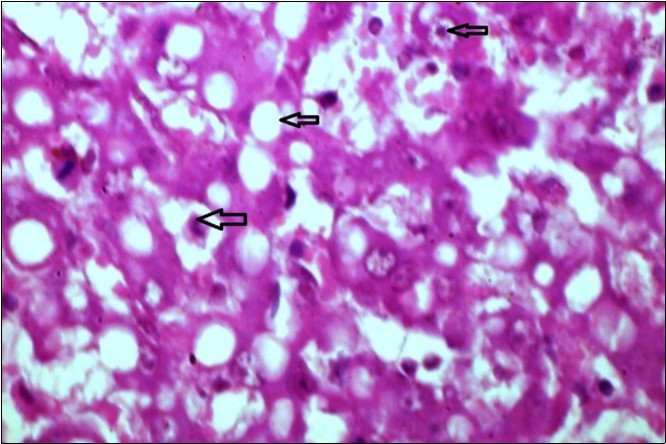

Figure 9.Tongue (dead cattle less than 1 year old) showed vesicular nuclei of stratum corium epithelium which suffering hydropic degeneration. Esinophlic intranuclear inclusions were seen surrounded by hallow zone(arrows). (Hematoxylin and fuchsin X 60)